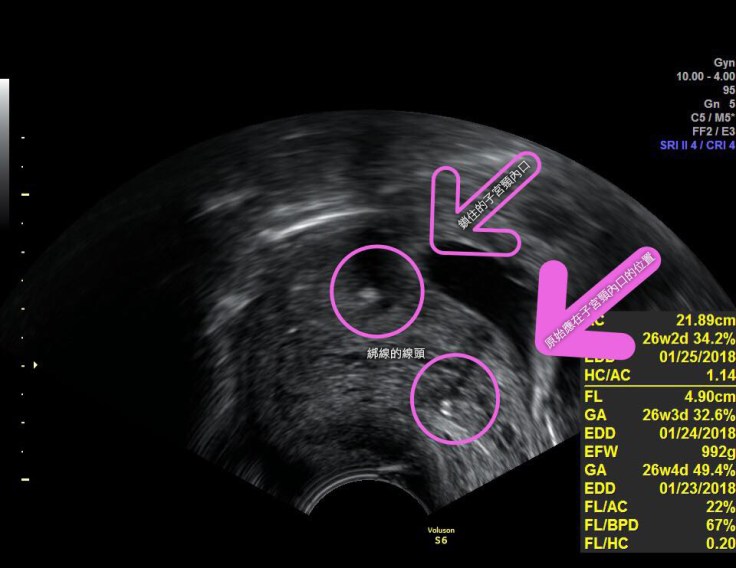

26週了 這是上次這個故事的媽咪 惱人的子宮頸閉鎖不全

從超音波照片上應該可以看到綁線的線頭(圈起來的地方)

被線頭鎖住的子宮頸內口(空心箭頭處)

還有已經鬆開閉鎖不全的原始子宮頸內口該在的地方(實心箭頭處)